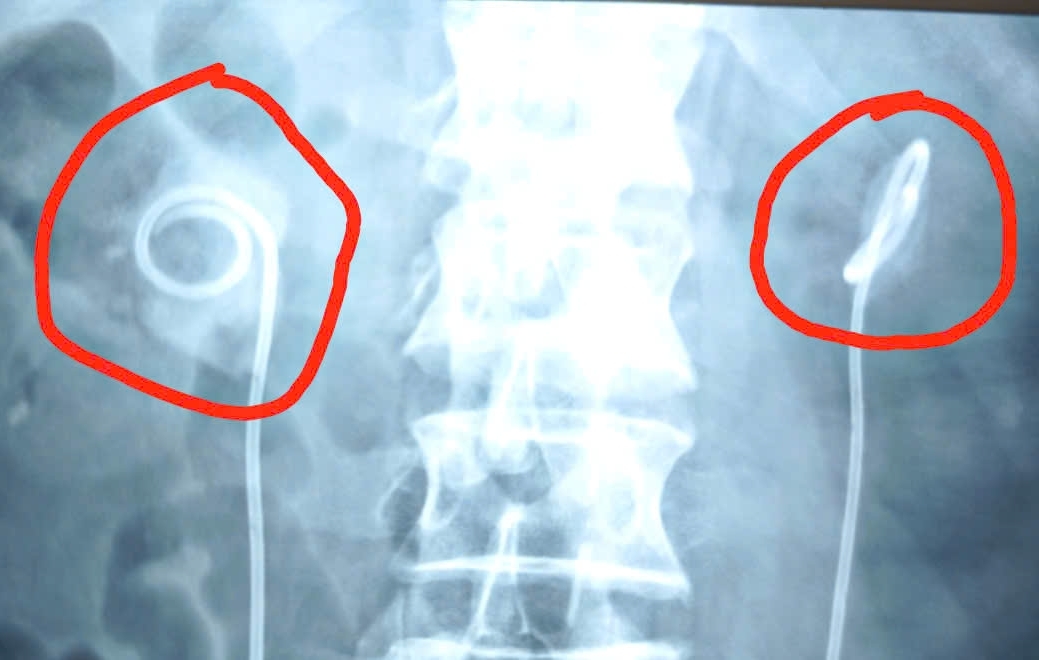

Bác sĩ Trần Duy Hiến, khoa Ngoại tổng hợp, Tiết niệu và Nam học cho biết, do ống JJ lưu quá lâu, không thể rút bằng phương pháp thông thường. Bệnh nhân được chỉ định chụp CT và kết quả cho thấy: sỏi hình thành bám chặt quanh ống, chiếm gần toàn bộ đài bể thận hai bên. Thận phải có viên sỏi lớn tới 34x29 mm, thận trái 20x13 mm, kèm nhiều viên nhỏ khác. Thận phải còn bị ứ nước độ 3 – mức độ nặng.